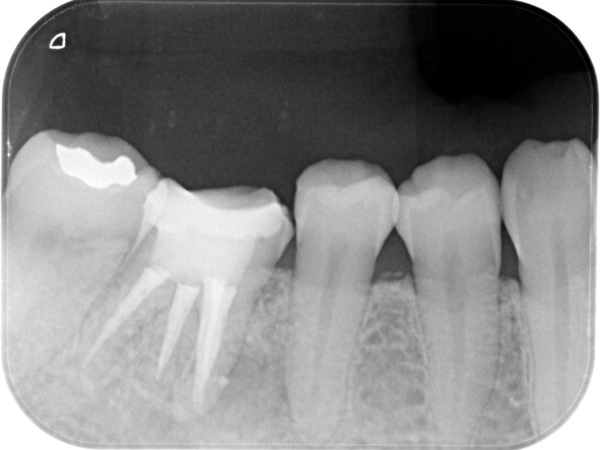

根管治療終了時